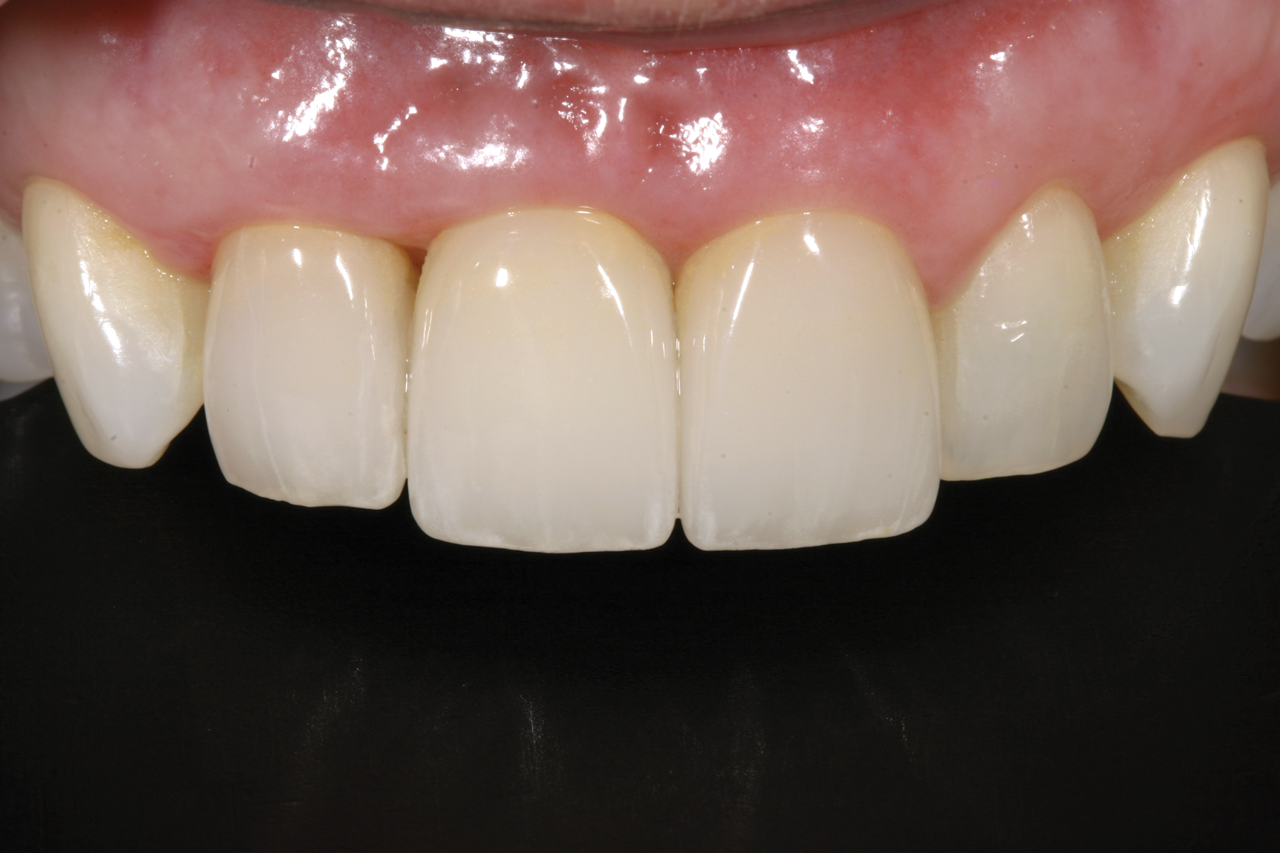

Fig 5. Successful final clinical result of the implant restoration and adjacent teeth.

Figure 5